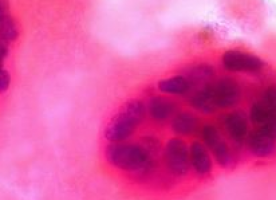

The researchers found that the mitochondrial networks within several different lung cancer cell lines were highly fragmented, compared to normal lung cells.

Cancer cells had low levels of mitofusin-2 (Mfn-2), a protein that promotes fusion by tethering adjacent mitochondria, and high levels of dynamin-related protein (Drp-1), which initiates fission by encircling the organelle and squeezing it into two discrete fragments. The Drp-1 in cancer cells also tended to be in its most active form.